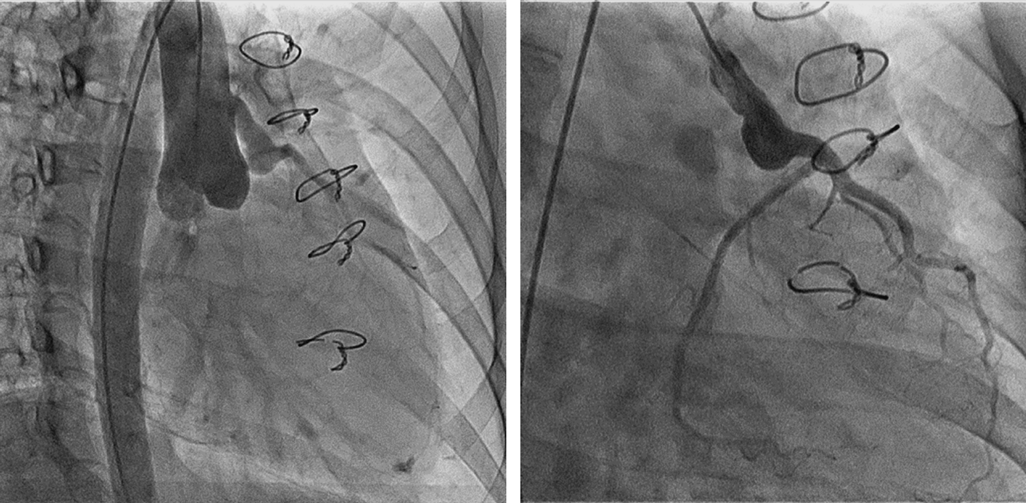

Her clinical record presented the first surgical treatment of ALCAPA using Takeuchi repair when she was one-month-old. She then underwent the following reoperations at the previous hospital: (1) residual coronary shunt closure in the reconstructed root with mitral repair when she was 1 year old; (2) the right pulmonary arterial plasty when she was 2; and (3) residual coronary shunt closure with the right ventricular outflow tract (RVOT) reconstruction using a tissue engineering patch when she was 14. However, a large patch without a leaflet caused severe pulmonary regurgitation (PR) with enlarged RV, resulting in severe tricuspid regurgitation (TR) caused by tricuspid annular dilatation. Six months before the pregnancy, she took another operation in our hospital when she was 29 year old. An expanded polytetrafluoroethylene (ePTFE) valved conduit, 22 mm of internal dimension, was used for PR repair and the Contuor 3D annuloplasty ring (Medtronic, Minneapolis, MN, USA) was applied for TR repair. The overall outcome of the RVOT reconstruction and the tricuspid valve plasty was excellent. The cardiothoracic ratio on chest X-ray was 59% and 50% before and 3 months after the operation, respectively (Fig. 1). Analogously, RV end-diastolic volume index by cardiac magnetic resonance (CMR) imaging improved from 189 mL/m2 to 64.2 mL/m2, and RV end-systolic volume index from 78.3 mL/m2 to 24.6 mL/m2. PR fraction improved from 43.4% to 4.5% (movie 1, 2). Cardiac output index increased from 1.7 L/min/m2 to 3.51 L/min/m2 calculated in CMR through the operation.

Fig. 1 Chest X-ray

The cardiothoracic ratio was 59% (left) and 50% (right) before and 3 months after the operation.